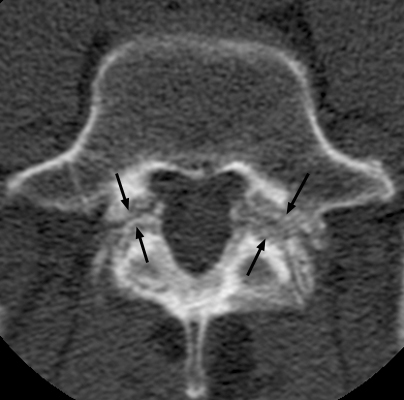

Incomplete Ring Sign

Spondylolysis

CT of the spine with discontinuity of the lateral bodies of the vertebrae with the posterior elements at the same level. This simple sign of discontinuity has been labeled the incomplete ring sign and is specific for fracture of the pars interartcularis (spondylolysis) as seen on CT scans. This sign is usually readily apparent because on no scan will the entire cortical ring be identified. Other causes such as spina bifida occulta can also appear as an incomplete ring, but with the discontinuity at a different site thereby making differentiation easy.

bulletLangston JW, Gavant ML: "Incomplete ring" sign: a simple method for CT detection of spondylolysis. J Comput Assist Tomogr 1985 Jul-Aug;9(4):728-9.          [See related articles]